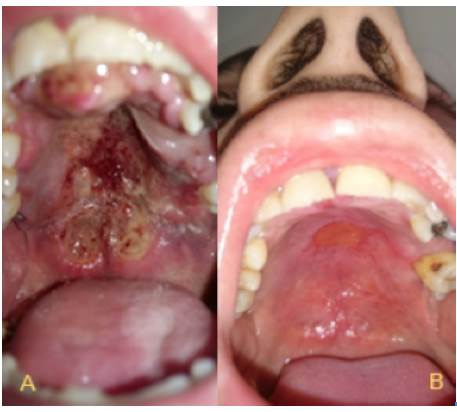

This case presents a 31-year old mestizo male patient, born in Fusagasugá, Colombia, with a history of inhaled cocaine and tobacco abuse. He works as a painter, with constant exposure to inhaled chemicals. The month prior to consultation, he was treated for acute sinusitis with amoxicillin for 10 days due to bilateral nasal obstruction and occasional epistaxis. Three weeks before consultation, he noted a painful ulcer in the hard palate, although, no systemic symptoms were reported. On general examination he was cachectic but stable, and presented with hyponasal speech. Rhinoscopy showed a bilateral mass in the nasal cavity with septal perforation in Cottle zones 2 - 3. Hard and soft palate showed a necrotic lesion with irregular borders, mucosa swelling without active bleeding. He had no palpable adenopathy on head and neck (Figure 1).

The final staging was T4, N1, M0, ECOG 1, IPI of low/intermediate-risk in a patient with poor health condition. The patient underwent chemotherapy with SMILE protocol (Table 1). Only 2 courses of SMILE were administered with adequate tolerance and some side effects, which were easily managed, such as queasiness, vomiting, weight loss and alopecia. Figure 4 shows the improvement of the lesion seven months after initiation of treatment; finally, after ten months of clinical and radiological surveillance, there was a complete remission of the lesions in oral and nasal cavity. In addition, the patient reported improvement of nasal obstruction and pain in the palate by 90%, but left amaurosis was persistent.